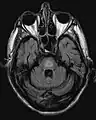

El antecedente de haber sufrido hiponatremia, sumado a las características clínicas previamente descritas son el sello de la enfermedad. La resonancia magnética puede mostrar ciertos cambios a nivel del parénquima cerebral, como es el aumento en la intensidad a nivel pontina[4]

Mielinolisis central pontina

Resonancia que muestra aumento de la intensidad de la imagen bilateral y simétrica a nivel del caudado (flecha pequeña), putamen (flecha larga) con extensión hasta el globo pálido, sugerente de mielonisisi extrapontina